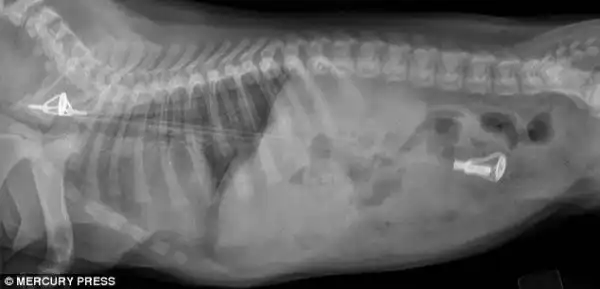

Лабрадор, проглотивший 3 массивных рыболовных грузила

Три 200-граммовых грузила извлеченные из его желудка